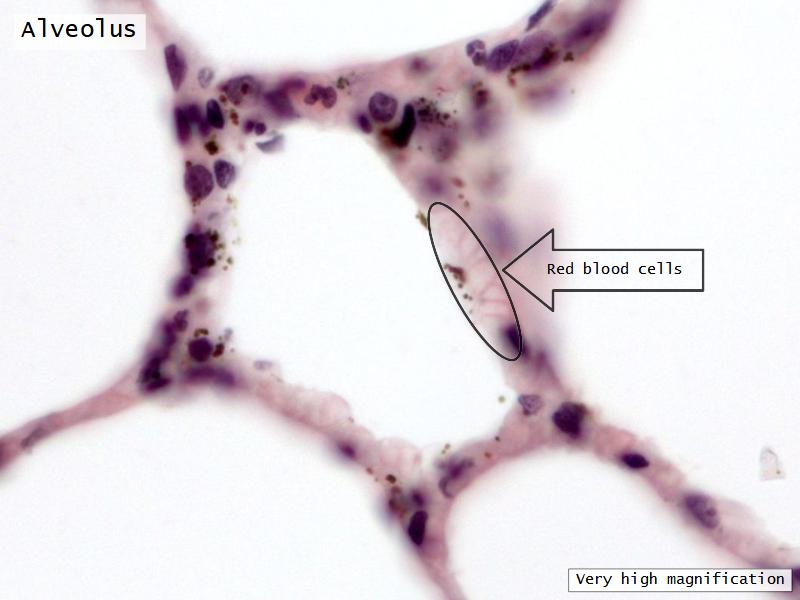

The cardiovascular system needs to be connected to the respiratory system.Path of O2 and CO2

Components of the Blood-Air Barrier?

- Alveoli

Lungs